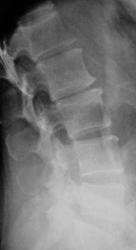

Пол пациента: Женский пол Тип патологии: Другое Область исследования: Скелетно-мышечная система Методы исследования: Rg Боли в пояснице, пациентка направлена на рентгенографию ПОП https://radiomed.ru/sites/default/files/styles/case_slider_image/public/user/12/2.dscn1426a.jpg?itok=e7leiWEL https://radiomed.ru/sites/default/files/styles/case_slider_image/public/user/12/3.dscn1427.jpg?itok=VzSynAjt https://radiomed.ru/sites/default/files/styles/case_slider_image/public/user/12/4.dscn1427a.jpg?itok=6MsG_uLx ID:27772 Чт, 11/04/2013 - 19:54 #1 Алексей Станисл... Не на сайте Был на сайте: 6 лет 3 дня назад Зарегистрирован: 11.08.2012 - 20:33 Публикации: 1903 Даже и боюсь сказать, такие баталии обычно по этому поводу - спондилолиз L4, L5? Не говоря о пресловутом остеохондрозе и "развороте" суставов L3-4, L4-5 во фронтальную плоскость...))) Но раз все молчат... С уважением, Пт, 12/04/2013 - 01:34 #2 Катенёв Валенти... Не на сайте Был на сайте: 7 лет 2 месяцев назад Зарегистрирован: 22.03.2008 - 22:15 Публикации: 54876 Алексей Станиславович wrote: Даже и боюсь сказать, такие баталии обычно по этому поводу А баталий вот и нет..., один Ваш коммент уважаемый коллега, и всё... Пт, 12/04/2013 - 08:35 #3 Алексей Станисл... Не на сайте Был на сайте: 6 лет 3 дня назад Зарегистрирован: 11.08.2012 - 20:33 Публикации: 1903 Не знаю, я столько "красных тряпок" накидал... Неужели все правильно (и больше ничего не видно)? С уважением, Пт, 12/04/2013 - 17:57 #4 Катенёв Валенти... Не на сайте Был на сайте: 7 лет 2 месяцев назад Зарегистрирован: 22.03.2008 - 22:15 Публикации: 54876 Алексей Станиславович wrote: Но раз все молчат... Значит тайну великую хранят...

Даже и боюсь сказать, такие баталии обычно по этому поводу - спондилолиз L4, L5? Не говоря о пресловутом остеохондрозе и "развороте" суставов L3-4, L4-5 во фронтальную плоскость...